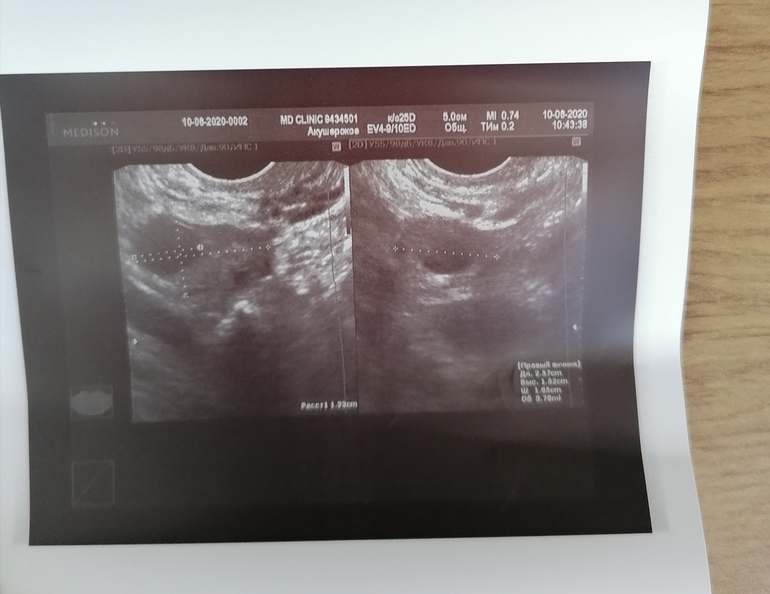

Сходила сегодня на узи к своему врачу у которой веду все беременности. Вообщем у меня 3 ДФ на 6 ДЦ. Овуляция будет ранняя однозначно. Надо теперь наростить эндометрий и вперёд. Пойду ещё на 11 ДЦ.

И правый, но тут не чётко видно правда

Совершенно точно это не ЖТ и не кисты. Включали и кровоток смотрели.